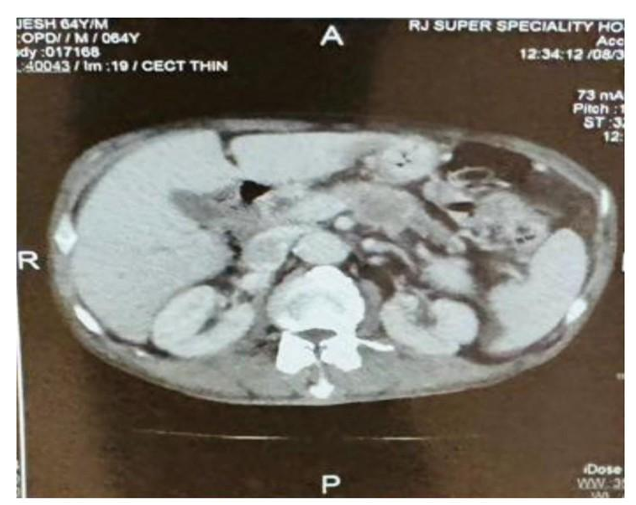

Herpes Zoster Mimmicking Renal Colic

1. Abstract 1.1. Back Ground Herpes zoster, or shingles, is a painful viral infection caused by the reactivation of the varicella-zoster virus (VZV), the same virus as chickenpox, resulting in a blistering rash, often on one side of the body or face, accompanied by burning pain, tingling, and itching.